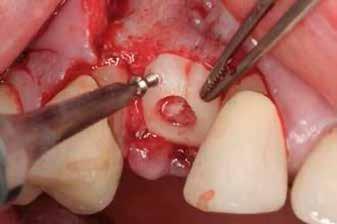

A fogak eltávolítása minimálinvazív módon történt, amelynek során a parodontális rostokat egy periotom segítségével átvágtuk, így lebenyes feltárásra nem volt szükség (3. a–b ábrák) . Az implantátumokat a frissen eltávolított fogak alveolusaiba ültettük be. A foghúzást követően minden alveolust alaposan ellenőriztünk az endodontiai, vagy parodontális eredetű gyulladásos szövetmaradványok eltávolítása érdekében, majd fiziológiás sóoldattal bőségesen átöblítettük. Megfelelő előfúrást követően a kerámiaimplantátumokat 30 fordulat/perc sebességgel és 35 Ncm behajtási nyomatékkal helyeztük be (4. a–b ábrák) . A réseket csontpótlóval töltöttük ki (Maxresorb ® 0,5–1,0 mm szemcseméret, 0,5 cm 3 térfogat, Straumann ®; 6. ábra ).

3. ábra: Intraorális kiindulási állapot. – 4. ábra: A terület intraorális nézetből. 5. ábra: A lebenyes feltárást követően laterális és vertikális csonthiány látszik a 1.4 területén. – 6. ábra: Az Easy Bone Collector egy egyedi műszer, amely trepánfúrót, belső hűtést, kerámia csapágyakat és integrált lágyrészvédelmet tartalmaz. Mindez megkönnyíti a csontlemezek eltávolítását. – 7. ábra: A semilunaris technika és az Easy Bone Collector együttes alkalmazása több kortikális csontlemez kinyerését teszi lehetővé a retromoláris régióból.

Javasolt, hogy a lehető legpontosabban ragaszkodjunk a hangár technika műtéti protokolljához. Miután a csontlemezeket oszteoszintézis csavarokkal rögzítettük, az okkluzális csontlemezt egy trepán fúróval átfúrjuk (lehetőleg az implantátum átmérőjével megegyező méretben), majd az imp-

lantátumot ezen a nyíláson keresztül helyezzük be a korábban előfúrt helyre, amelyet előtte autológ csontrészecskékkel töltünk fel.